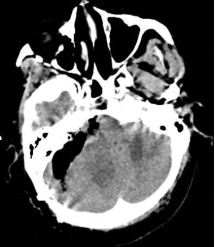

听神经瘤术前核磁 术后CT